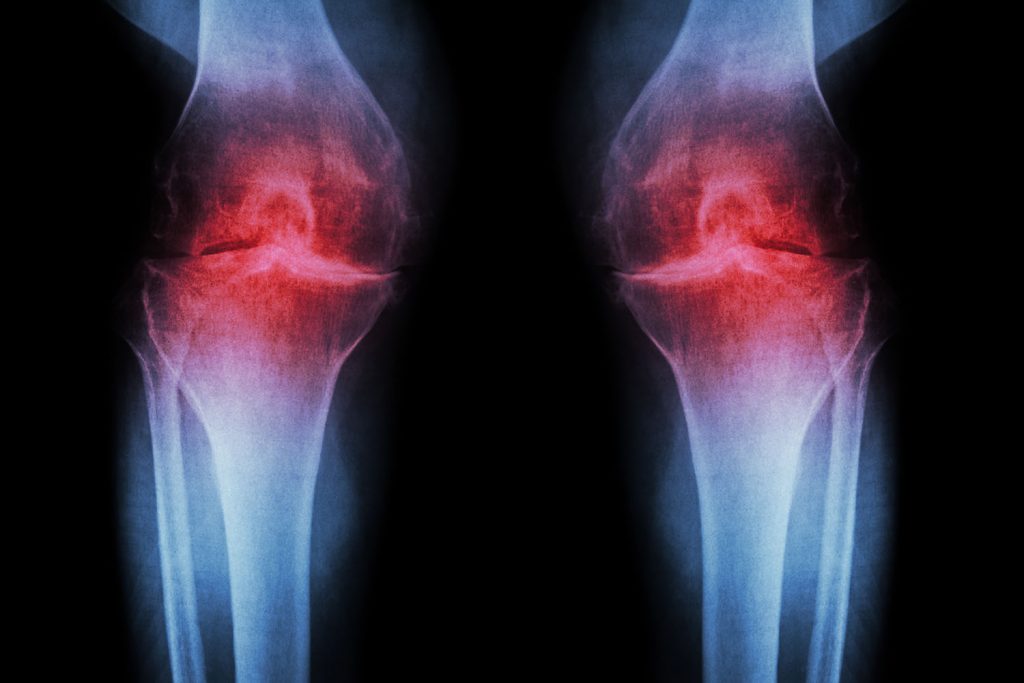

Osteoartrita este o afectiune degenerativa caracterizata prin distrugerea in timp a cartilajului care protejeaza suprafata articulara. Odata ce cartilajul se subtiaza, oasele se ating si la fiecare miscare apare fenomenul de frecare intre acestea, lucru care provoaca durere. Aceasta afectiune este cea mai comuna cauza a durerilor articulare la varstnici, putand afecta atat articulatiile mari, cat si pe cele mici. Din pacate, osteoartrita in stadiile avansate este extrem de invalidanta, astfel incat calitatea vietii acestor pacienti este afectata.

Poliartrita reumatoida este o afectiune inflamatoare autoimuna, ce afecteaza articulatiile mainilor si picioarelor si apare frecvent la populatia cu varsta cuprinsa intre 25 si 50 de ani. Cauza acestei boli este o alterare in sistemul imunitar care ataca articulatiile, cu timpul aparand eroziuni ale cartilajului si oaselor. Odata ce boala avanseaza, au loc tumefactii si deformari articulare extrem de dureroase si invalidante. Aproximativ 30% dintre cei afectati prezinta si noduli reumatoizi specifici. Desi tabloul clinic al acestei boli este destul de usor de recunoscut pentru diagnosticul de certitudine, este nevoie de analize de laborator (markeri specifici).